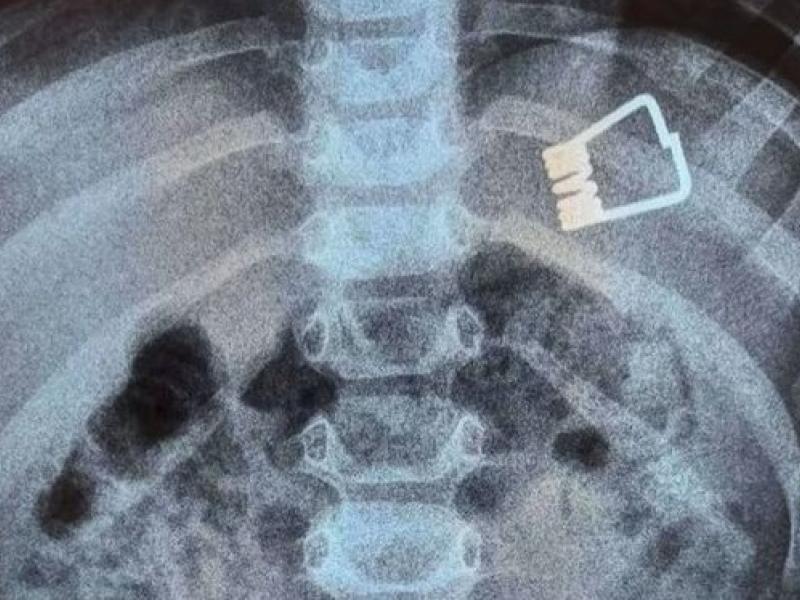

Λήμνος: 2χρονο παιδί κατάπιε μανταλάκι - Πώς το αφαίρεσαν (video)

Η πρωτοποριακή μέθοδος που χρησιμοποίησαν οι γιατροί για να αφαιρέσουν το μανταλάκι χωρίς χειρουργική επέμβαση

Αίσιο τέλος είχε η περιπέτεια ενός αγοριού από τη Λήμνο, ηλικίας 2 ετών, το οποίο κατάπιε ένα έλασμα από μανταλάκι.

Οι γιατροί στο Ιπποκράτειο Νοσοκομείο στη Θεσσαλονίκη όπου και μεταφέρθηκε εσπευσμένα το παιδί κατάφεραν να αφαιρέσουν το ξένο αντικείμενο από το στομάχι του, χωρίς να προβούν σε χειρουργική επέμβαση, αλλά με τη βοήθεια ενός ενδοσκοπίου τελευταίας γενιάς, όπως αναφέρει ρεπορτάζ της ΕΡΤ3.

Το περιστατικό σημειώθηκε, κάτω από αδιευκρίνιστες μέχρι στιγμής συνθήκες, στο σπίτι του παιδιού στη Λήμνο. Το δίχρονο αγόρι μεταφέρθηκε με Super Puma από το νησί στη Θεσσαλονίκη, όπου και διακομίσθηκε στο Ιπποκράτειο Νοσοκομείο.

«Όταν το παιδί έφτασε εδώ, αμέσως κινητοποιηθήκαμε, ενημερώσαμε τους αναισθησιολόγους, είχαμε έτοιμο το χειρουργικό κρεβάτι. Το παιδί έπρεπε να είναι νηστικό 6 με 8 ώρες και προβήκαμε στην αφαίρεση ενδοσκοπικά του ξένου σώματος», δήλωσε στην ΕΡΤ 3 ο Ιωάννης Ξηνίας, αναπληρωτής καθηγητής Παιδιατρικής Γαστρεντερολογίας.